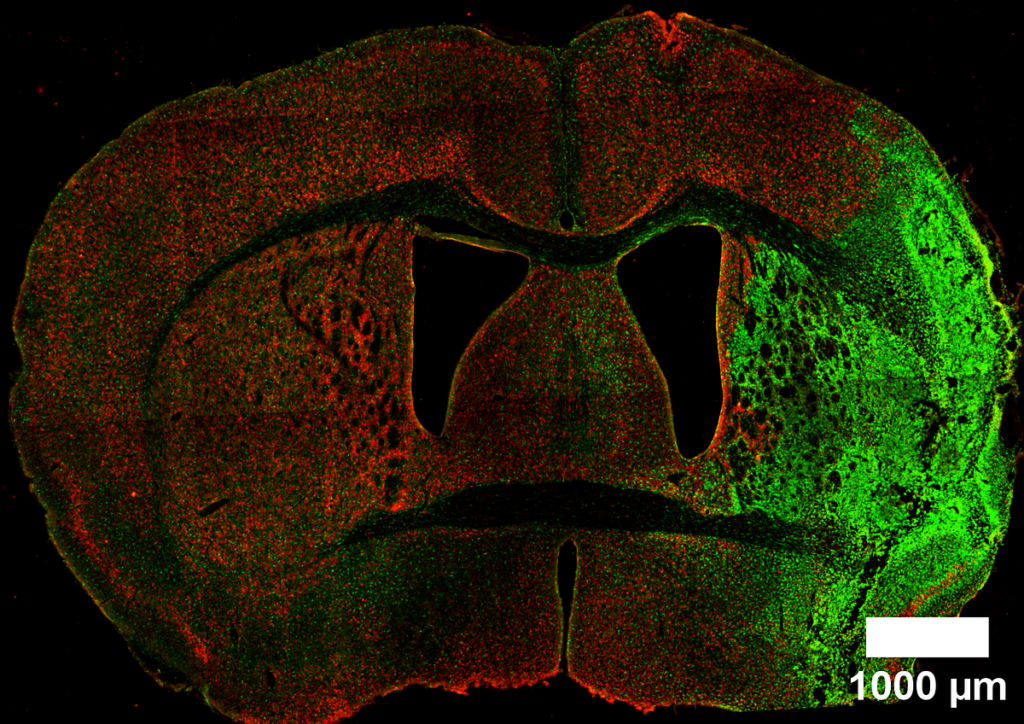

Osservando i dati presentati nel grafico di destra di Figura 5 rivela una discrepanza tra i nostri risultati empirici e la nostra comprensione teorica dell’argomento. Sulla base delle conoscenze consolidate, ci aspettiamo una maggiore probabilità di conta cellulare diversa da zero nella zona subventricolare (SVZ) dell'emisfero ipsilaterale, soprattutto a seguito di un infortunio. Questo perché la SVZ ipsilaterale diventa tipicamente un centro di attività cellulare, con una significativa proliferazione cellulare dopo la lesione. I nostri dati, che indicano conteggi prevalenti diversi da zero in questa regione, supportano questa aspettativa biologica.